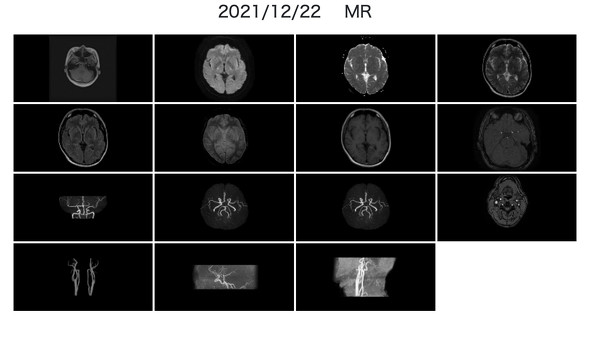

そこでスマートスキャンでは装置のシェアリングを行うだけではなく、映像データをネット上でセキュアに共有。脳のMRI、MRA画像は、それぞれ放射線科と脳神経内科の医師が両方セットで必要になるというが、それぞれの医師が自分の空いている時間にアルバイトで読影するクラウドワークの仕組みを提供している。

利用者は会員登録し、予約した時間、予約した場所に訪れ、MRIの中に15分ほど入れば、あとは着替えて帰るだけ。登録した会員IDでログインすると、自分の映像をいつでも確認でき、また数日もすると読影結果が反映される。

しかしスマート脳ドックは、装置と読影する医師、両方の空き時間を活用するため、MRI、MRAによる脳と血管の診断を税込1万9250円で提供している。